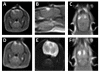

Methods: A combination of analytical, numerical, and experimental techniques were performed to investigate high-frequency irreversible electroporation (H-FIRE). A theoretical model for determining transmembrane potential in response to arbitrary electric fields was used to identify optimal burst frequencies and amplitudes for in vivo treatments. A finite element model for predicting thermal damage based on the electric field distribution was used to design non-thermal protocols for in vivo experiments. H-FIRE was applied to the brain of rats, and muscle contractions were quantified via accelerometers placed at the cervicothoracic junction. MRI and histological evaluation was performed post-operatively to assess ablation.

Results: No visual or tactile evidence of muscle contraction was seen during H-FIRE at 250 kHz or 500 kHz, while all IRE protocols resulted in detectable muscle contractions at the cervicothoracic junction. H-FIRE produced ablative lesions in brain tissue that were characteristic in cellular morphology of non-thermal IRE treatments. Specifically, there was complete uniformity of tissue death within targeted areas, and a sharp transition zone was present between lesioned and normal brain.